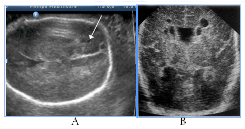

Obviously, that GPO of hydranencephaly and schizencephaly were unfavorable, wherein only bilateral schizencephaly was accompanied with clinically significant macrocrania (head circumference 430mm, it was above 95th percents of the average gestational circumference) (Figure 3). In case of hydranencephaly the liquor pressure did not increase and remained normal size of the fetal skull.

Figure 3Destructive brain lesions, 3cases.

Figure 3 Destructive brain lesions, 3 cases. A) Hydranencephaly, total absence of cortical mantle and falx, saved diencephalon, hypothalamus and basal ganglia, wherein postnatal life was possible, by maintaining thermoregulatory functions, catamnesis - infant death in 3months. B) No structures of the brainstem, there are only remnants of supratentorial tissue, no sickle and cortical border, intranatal fetal death. C) Bilateral schizencephaly (type II, "open lip") with severe hydrocephalus and macrocrania, intranatal fetal death, clinically narrow pelvis, fetus-damaging operation.